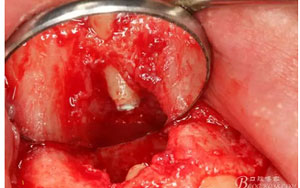

圖9.翻開角形瓣后,有骨壁缺損,囊壁有穿孔,這就是溢膿的竇道出口。

圖13.囊壁摘除后形成的骨腔,12牙根完全裸露在骨腔內(nèi)。

圖14.超聲骨刀切除根尖組織3mm。